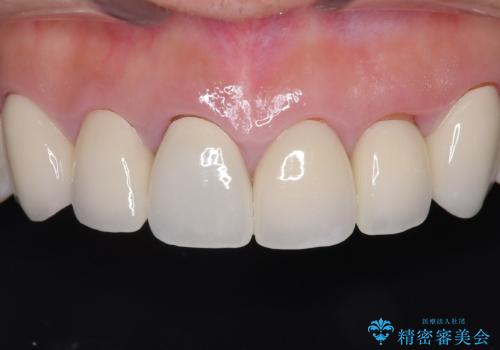

前歯の破折も1日で解決!抜歯即時インプラントで自然な笑顔へ

- 治療計画

- 前歯の痛みと破折を主訴にご来院されました。精密な診査の結果、歯の根元までひび割れが進行し、保存が困難であると診断。見た目にも関わる前歯を失うことへの患者様の不安を考慮し、抜歯と同時にインプラントを埋入する抜歯即時埋入インプラントによる治療計画を立案しました。これにより、歯がない期間を最小限に抑え、治療期間と身体への負担を軽減しながら、審美性の高い新しい歯を獲得することを目指します。

今回の治療では、まず原因となっていた前歯を慎重に抜歯し、その直後にインプラントを埋入しました。抜歯即時埋入は、歯を失うのとほぼ同時に新しい歯の土台を確保できるため、骨の吸収を防ぎ、仕上がりの美しさを保つ上で非常に有効です。また、治療当日に仮歯を装着することで、歯がない期間をなくし、患者様の精神的なご負担にも配慮しました。最終的に、周囲の歯と調和したオーダーメイドのセラミッククラウンを装着。機能性だけでなく、天然歯と見分けがつかないほどの自然で美しい前歯を取り戻していただけました。